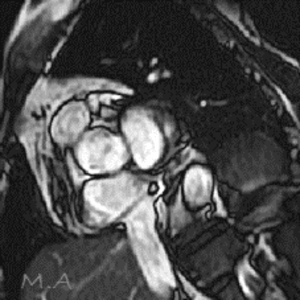

MRI

MRIとはMagnetic Resonance Imaging(磁気共鳴画像法)の略で、強力な磁石と電波を使って様々な角度から体の断面を画像化する検査です。

X線を使用しないため、放射線被ばくの心配がなく、軟部組織(筋肉、靱帯、神経など)の描出に優れており、がんの有無や広がり、転移の有無などを調べることができます。また、造影剤を用いずに血管を描出することが可能です。

部位や目的により異なりますが、検査時間は15分から40分程度です。複雑で高度な検査の場合は60分程かかる場合もあります。

当院ではCanon社製Vantage Fortian MRI 1.5Tを設置しており、主に脳血管疾患、脊椎疾患、閉塞性動脈硬化症などの下肢疾患、腹部疾患、心臓疾患、関節等の検査を行っています。